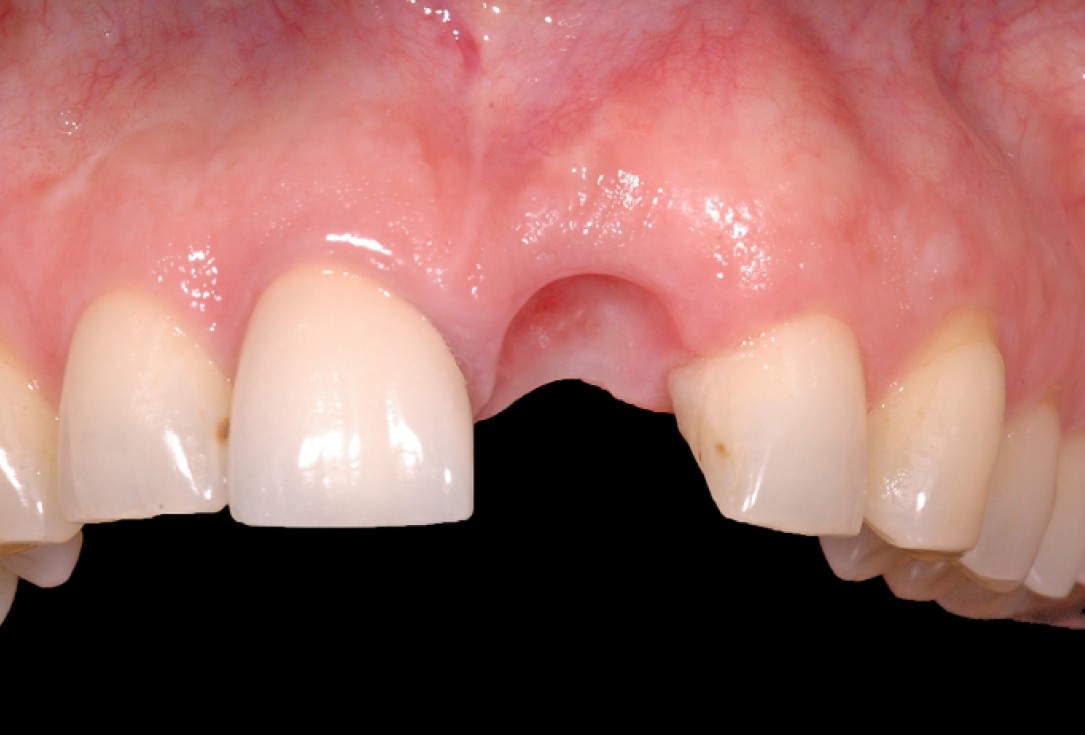

3/18 - Clinical situation 6-8 weeks after extraction, vestibular viewGBR together with soft tissue augmentation with mucoderm® and maxresorb® - Dr. S. Scherg